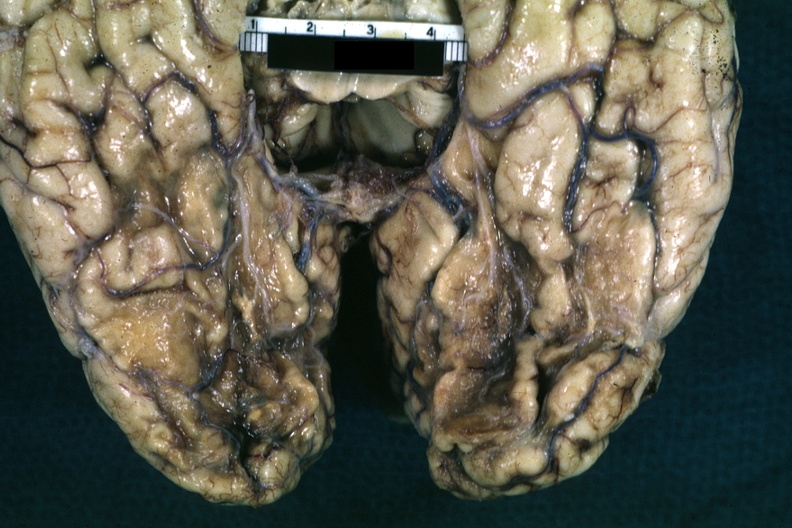

GROSS: NERVOUS: Brain: Infarct Remote: Gross fixed tissue close-up view of old infarcts over inferior surface of both temporal lobes associated with blindness